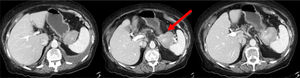

The patient is a 78-year-old woman with an allergy to non-steroidal anti-inflammatory drugs and a history of hypertension, type 2 diabetes mellitus and atrial fibrillation. She reported increasing abdominal pain over the previous 3 months located in the epigastrium and left hypochondrium, which did not subside with habitual analgesia and was associated with anorexia, nausea, vomiting and a weight loss of 4 kg. Lab work-up showed no relevant alterations. Thoracoabdominal CT scan revealed a 60 mm solid vascularized lesion in the portal phase between the greater curvature of the stomach and the splenic hilum, which it displaced without infiltrating. The lesion presented small satellite and periceliac lymphadenopathies. The findings indicated a possible stromal tumor (GIST) without ruling out association with the pancreas (Fig. 1). Endoscopic ultrasound-guided fine-needle aspiration provided evidence of lymphoid tissue with aggregates of epithelioid histiocytes, CD68+ and negative GIST markers (chronic inflammatory reaction with non-caseating histiocytic granulomas). Given the uncertain diagnosis, the patient’s symptoms and the impossibility to rule out malignancy, we decided to operate after presenting the case to a multidisciplinary committee. The initial laparoscopic approach was converted to a bilateral subcostal laparotomy due to hemodynamic instability and episodes of sustained ventricular tachycardia. We observed diffuse retroperitoneal granulomatous infiltrate and 3.5 L of ascites. Intraoperative peritoneal biopsies were negative for malignancy and reported as fibroconnective tissue with chronic inflammation, lymphoid and presence of granulomas with multinucleated giant cells. Distal pancreatectomy and splenectomy were performed. During postoperative ICU care, the patient required vasoactive drugs and amiodarone infusion due to an episode of atrial fibrillation. After favorable evolution, the patient was moved to the ward on the 3rd postoperative day and discharged on the 7th day without further incidents (Clavien-Dindo IVa). The histology study showed a smooth tumor measuring 60 × 50 mm dependent on the pancreas, with a focus of intratumoral calcification. Microscopically, the peripancreatic lymph nodes were observed to have granulomas rich in epithelioid cells, multinucleated giant cells, and chronic inflammation without necrosis. The morphology of the lesion indicated sarcoidosis (Fig. 2). The extending diagnostic tests of the histochemical study for acid-fast bacilli (Ziehl-Neelsen and Fite-Faraco) were both negative, which confirmed the final diagnosis of sarcoidosis. Subsequent follow-up visits were favorable, with no surgical or endocrine/metabolic complications.